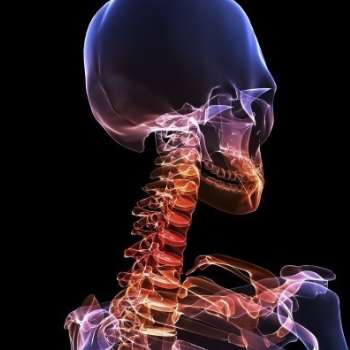

목디스크 증상 10가지

목디스크(경추 추간판 탈출증)는 목의 추간판이 탈출하거나 파열되어 주변 신경을 압박하는 질환입니다. 이로 인해 다양한 증상이 나타날 수 있으며, 각각의 증상은 환자에게 심각한 불편을 초래할 수 있습니다. 아래는 전문가적 입장에서 목디스크의 주요 증상 10가지를 상세히 설명하겠습니다.